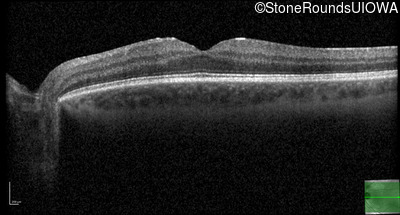

Optical Coherence Tomography - Right - 20/16

Exemplar / OCT Stack

OCT Stack

Optical Coherence Tomography - Left - 20/20 +2